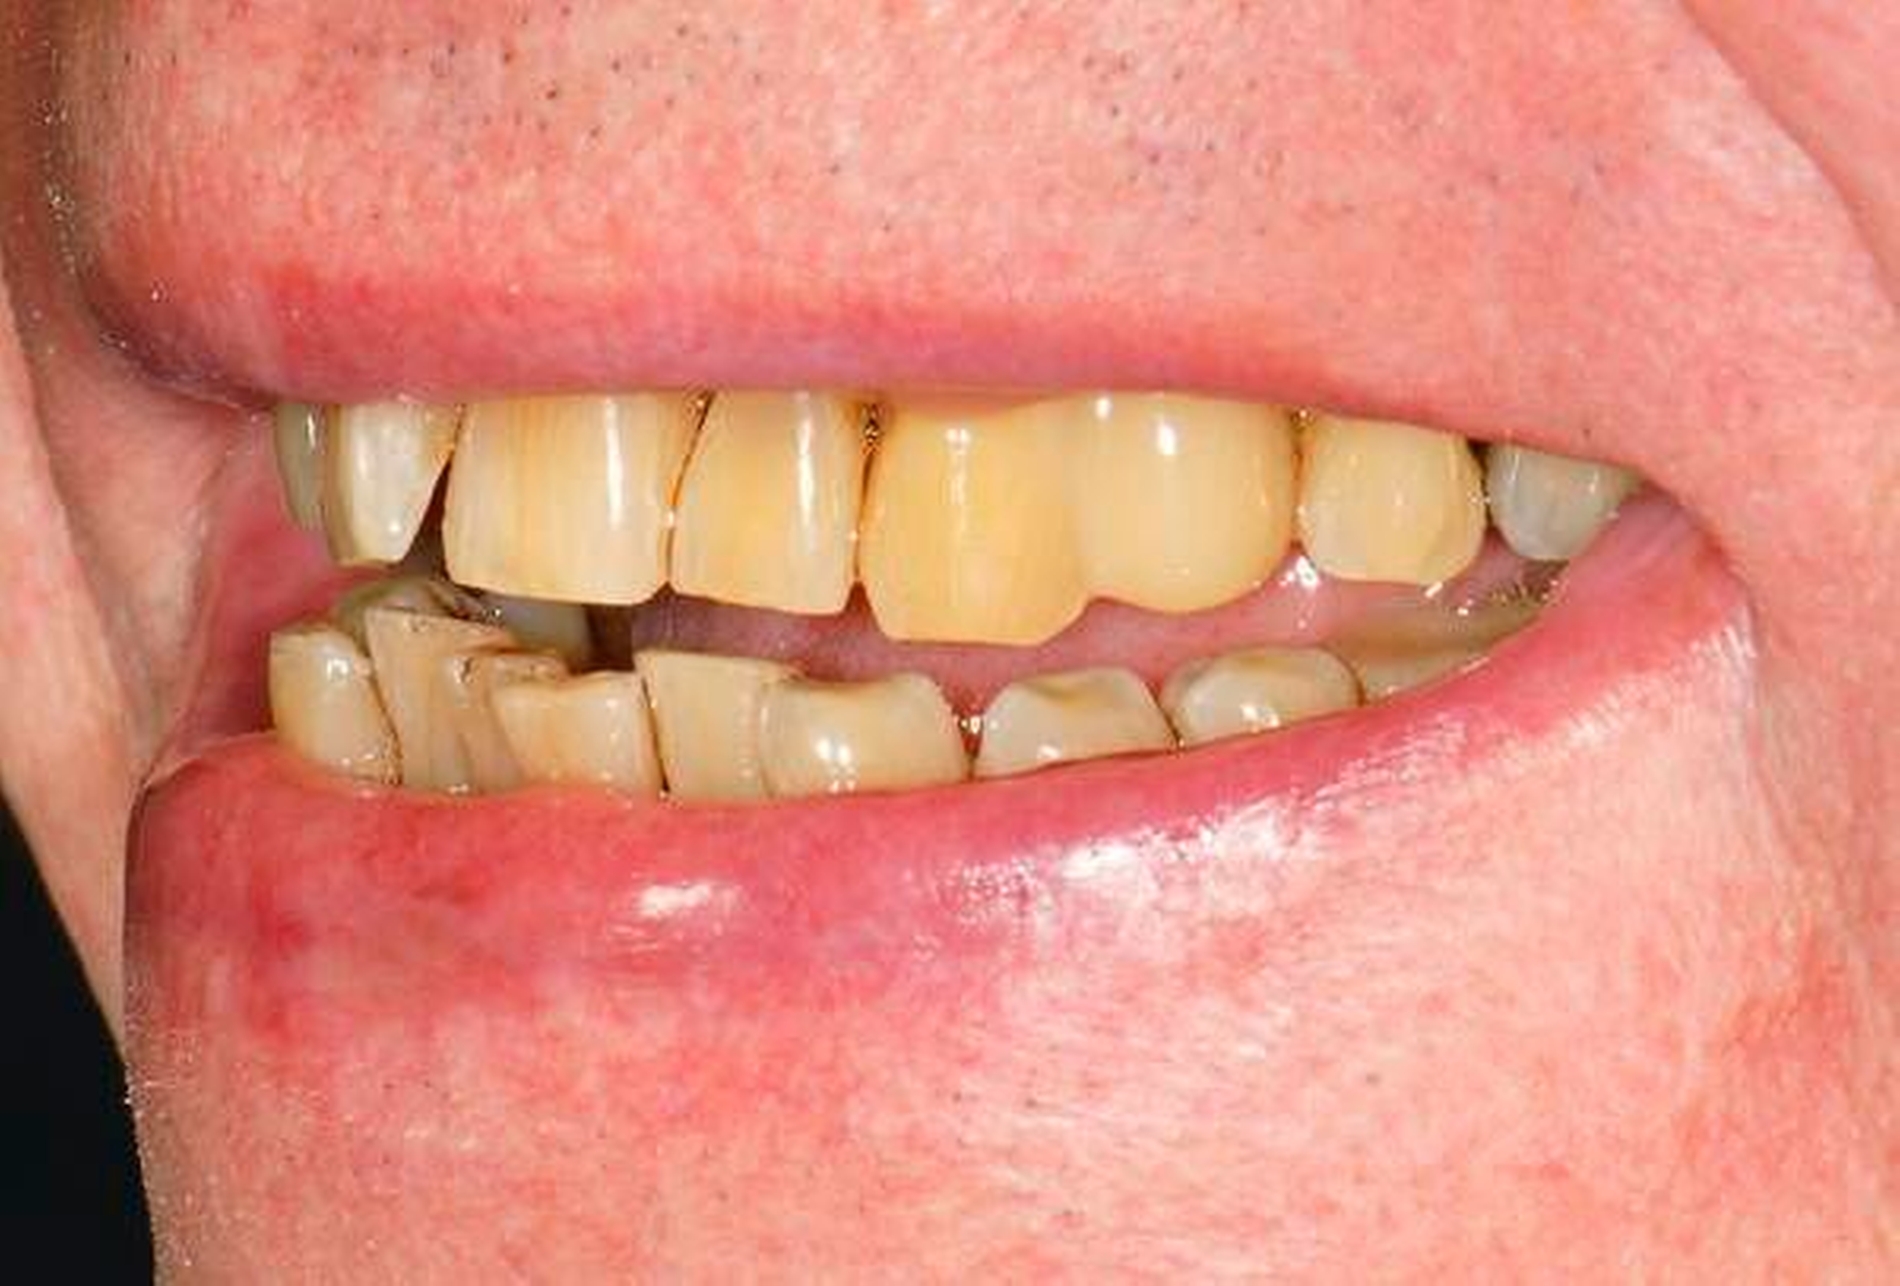

In den Abbildungen 1 bis 3 werden Optionen für frugale Interventionen auf restaurativem Sektor aufgeführt. Es handelt sich um direkte Vollüberkronungen im Frontzahnbereich (hier: hergestellt in R1-Technik / einphasig) (Abbildung 1), direkte Teilüberkronungen im Seitenzahnbereich (hier: hergestellt in R1-Technik / einphasig) (Abbildung 2), Reparatur-Restaurationen im Seitenzahnbereich (hier: hergestellt in R2-Technik / zweiphasig) (Abbildung 3). Technische Einzelheiten zur Vorgehensweise und den Ergebnissen sind an anderer Stelle beschrieben (Literatur siehe oben).

Am Beispiel von Abbildung 1 (stark zerstörte Zahnkrone eines Schneidezahns) kann das Prinzip der frugalen Intervention erläutert werden:

Früher wurde für die hier beschriebene Ausgangssituation folgendes Procedere gewählt:

Wurzelkanalbehandlung des vitalen Zahns als Voraussetzung für eine Stiftversorgung

Einsetzen eines Wurzelkanalstifts

Einsetzen einer indirekt gefertigten Stiftkrone

Durch die Erfolge der Adhäsiv- und Komposittechnik kann heute folgendermaßen vorgegangen werden:

Verzicht auf Wurzelkanalbehandlung / Erhaltung der Vitalität des Zahns

Verzicht auf Wurzelkanalstift

direkte minimalinvasive Kompositkrone (Verzicht auf indirekte Vorgehensweise)

Die potenziellen medizinischen und ökonomischen Vorteile dieser frugalen Intervention sind vielfältig:

Schonend: Die oralen Strukturen werden geschont und die Versorgung ist hinreichend stabil. Durch den Verzicht auf Wurzelkanalstifte wird das Wurzelfrakturrisiko reduziert. Zudem können Material-, Geräte- und Personalressourcen aus Praxis und Techniklabor, die beim klassischen Vorgehen anfielen, reduziert werden.

Bezahlbar: Hier ist anzumerken, dass die Kosten unter anderem von der zahnärztlichen Expertise abhängig sind: Zahnärzte, die mit direkten Restaurationen große Erfahrung haben, können zügiger und mit besserem Erfolg arbeiten als Kollegen mit geringerer Erfahrung auf diesem Gebiet; die Behandlung ist gleichwohl anspruchsvoll und deshalb nicht „billig“. Eine direkte Vorgehensweise kann, muss aber nicht automatisch zeit- und kostensparender sein als eine Versorgung mit indirekt hergestellten Werkstücken.

Gut genug: Ästhetische Feinheiten lassen sich bei direkten Restaurationen nicht immer in gleicher Perfektion einarbeiten wie bei indirekt gefertigten Kronen, auch die Stabilität des Hochglanzes lässt bei einigen Kompositpräparaten noch zu wünschen übrig. Andererseits erlauben die direkten Verfahren inzwischen mitunter sehr flexible Vorgehensweisen, die sich auch mit Farb- und Formkorrekturen von Zähnen kombinieren lassen. Die Erwartungen eines großen Teils der Patienten werden hinreichend erfüllt und die Nutzen-Risiko-Relationen wie auch die Aufwand-Kosten-Relationen erscheinen – wenn auch nicht durchgängig – so doch zumindest in vielen Fällen günstig.